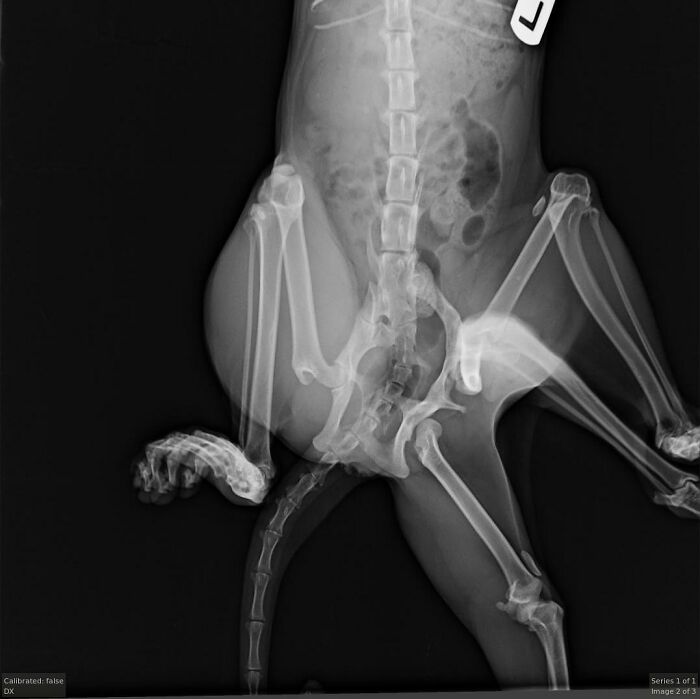

While in the womb, she absorbed a littermate, which caused her to have two extra legs and a second pelvis as she grew

At Windermere Veterinary Hospital, vets took X-rays and decided surgery was the best way to help Bitsy live more comfortably

Thanks to generous donors, Bitsy underwent a complex surgery to remove the extra limbs and pelvis